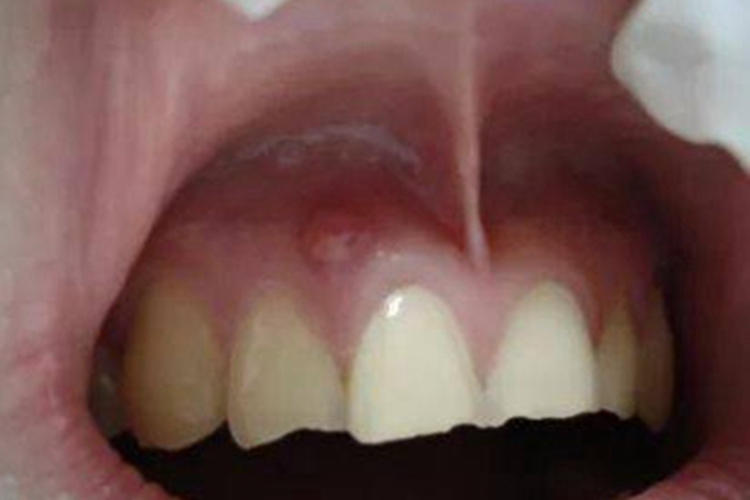

根尖囊肿患者临床可表现为牙龈处单发的囊肿,呈小疙瘩样,隆起于皮肤表面,边缘较整齐,与周围正常黏膜分界清晰,下方牙齿有叩痛感。

对于根尖囊肿牙龈上有个疙瘩的患者,需由专业医生通过取上颌窦根治术式切除囊肿。若病牙尚稳固,有保留可能,则行根尖切除或根管治疗,以避免囊肿再发。否则,应同时拔除病牙。